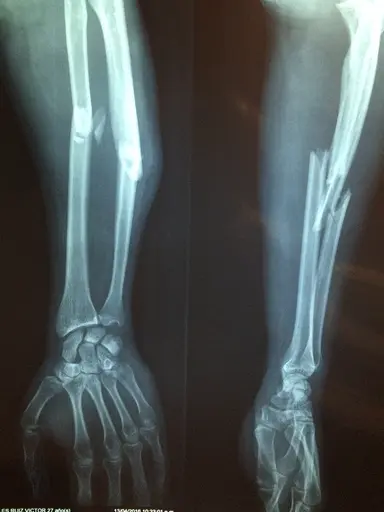

Children may think that bones are unbreakable.

Show children X-rays of broken bones and give them examples of where we wear extra protection to protect our bones.

Q3.What is this type of image called?

Q5.This person has had an accident. Look at the X-ray, what can you see?